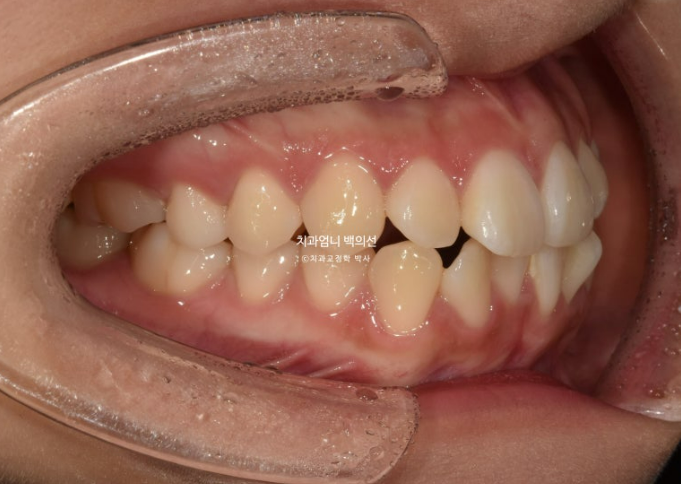

2023년 12월 앞니 부분교정을 원해서 내원한 분 입니다.

파란 화살표에 작은어금니 덧니도 보입니다.

아래 앞니가 많이 삐뚤 합니다.

어금니 교합이 그리 좋은 편은 아니었지만 환자분은 씹는데 불편함을 못 느끼는 상태였고 앞니 배열만 원하셨습니다.

기간과 비용, 환자분의 상황 모든 것을 고려하여 일부 포기하고 앞니 부분교정에 들어갔습니다.